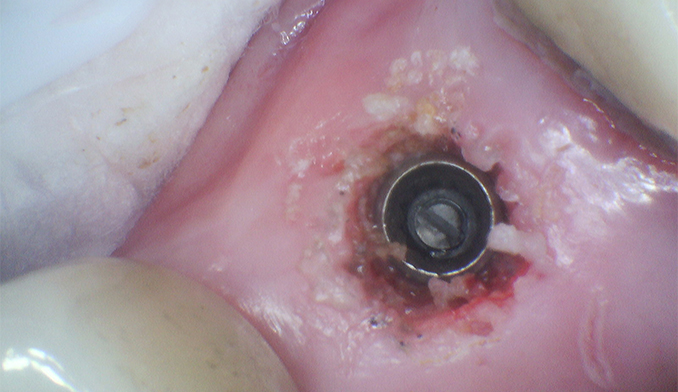

Molar Extraction, Bone Grafting, and Implant Placement

The patient’s lower right molar was severely damaged and could not be saved. After removing the tooth, we performed bone grafting to preserve the bone structure, ensuring a strong foundation for future treatment. Four months later, after proper healing, a dental implant was placed to restore function and maintain jaw health.